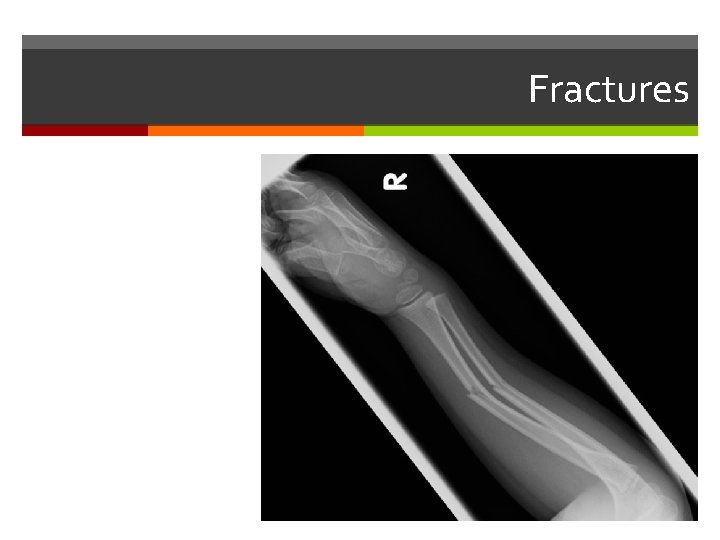

Fractures

Fractures Treated by Reduction: Closed Open